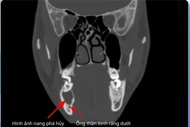

Răng lệch vào xoang hàm có thể gây viêm nhiễm nặng, cần phẫu thuật nội soi hiện đại để loại bỏ dị vật, hạn chế biến chứng.